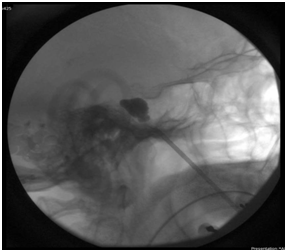

Patient presented to ER with a shooting, uncontrollable facial pain. Percutaneous balloon compression of the trigeminal ganglion was performed (Figure 2). After surgery, the patient had complete resolution of their pain, but later suffered a mild atypical facial pain 5/10 in the distribution of the V3. She was placed back on medical therapy with oxcarbazepine and pregabalin. Eight months post-balloon compression, the patient had gradually improved pain control.

Figure 2a Preoperatively, a skull computed tomography (CT) scan is achieved and the acquired images are introduced into the navigation system. Intraoperatively, a precise reference frame is strapped firmly to the patient’s forehead. The preliminary CT images are registered in the system, and cannulation is performed under the guidance of the navigation system.

Figure 2b Using image guidance, we navigated the needle to percutaneously access the foramen ovale by the use of a single tract for successful completion of balloon compression of the trigeminal nerve.